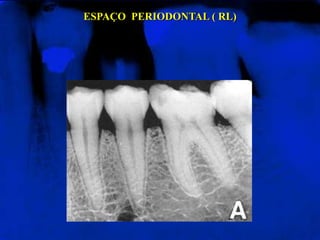

ESPAÇO PERIODONTAL ( RL)

LÂMINA DURA (RO)

Representa a porção da parede do alvéolo onde se inserem

as extremidades externas das fibras periodontais. Apresenta-

se radiograficamente como uma linha radiopaca fina que se

continua com as cristas ósseas alveolares.

LÂMINA DURA (RO) Representaa porção da parede do alvéolo onde se inserem as extremidades externas das fibras periodontais. Apresenta- se radiograficamente como uma linha radiopaca fina que se continua com as cristas ósseas alveolares.